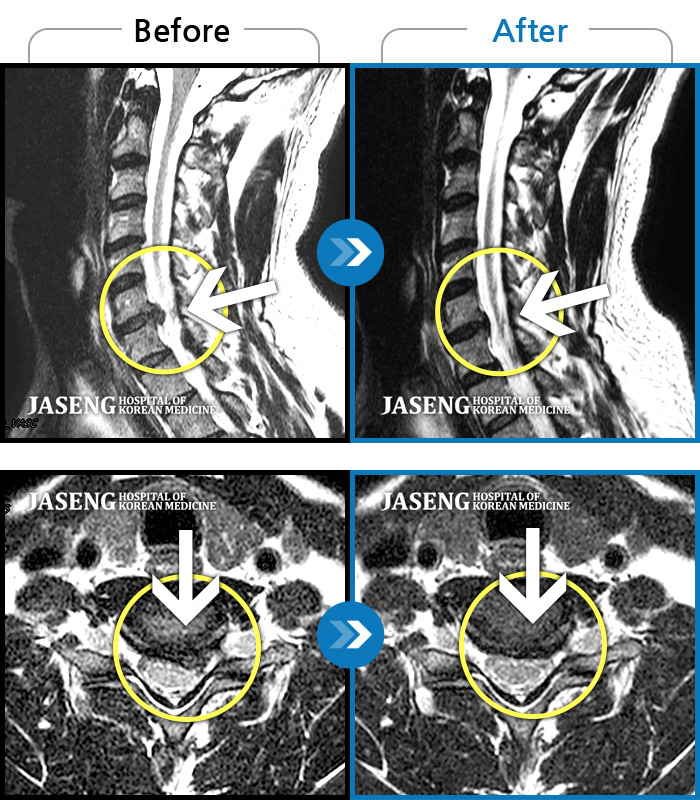

자생 비수술 한방통합치료 후

터진디스크가 흡수된 모습

비수술 치료만으로

터진 디스크 흡수

심한 통증과 전기에 감전된 듯한 저림이 있음

2012.06.14 ~ 2014.04.19

Before

After

목 통증과 왼쪽 팔에서 손가락까지 저림

2011.09.27 ~ 2012.01.19